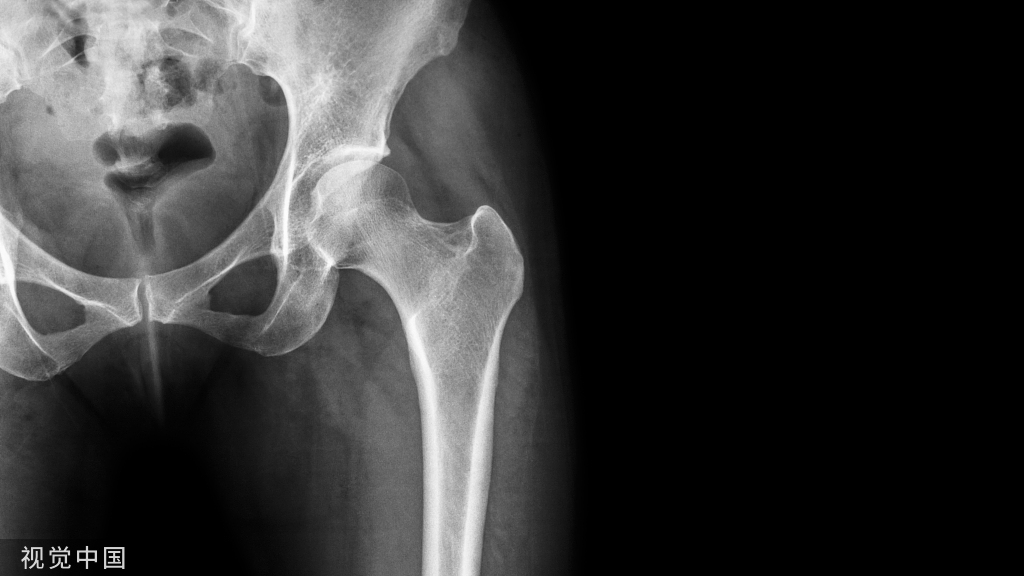

病人女性,外伤后骶尾部疼痛,dr片示骶尾关节对应关系差,骶5椎体欠规则。ct重建示骶5椎体粉碎性骨折!

X线